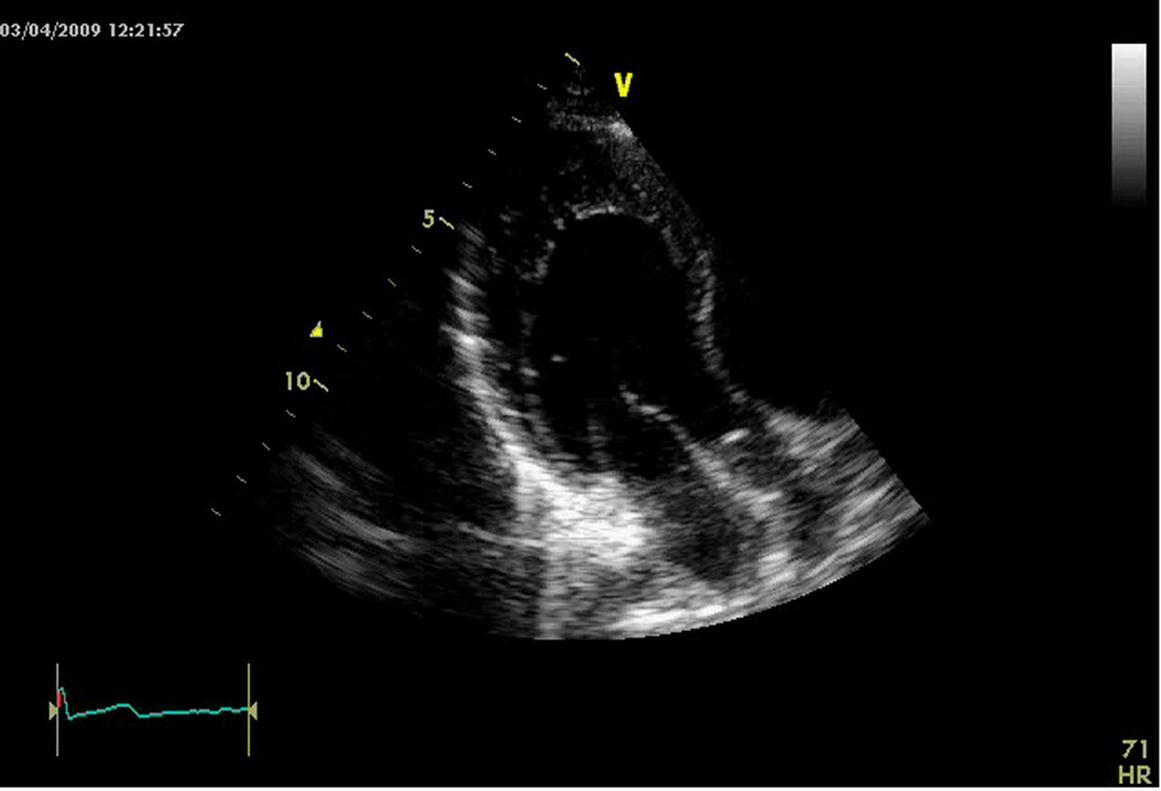

Rest electrocardiogram showed sinus tachycardia 110/m and no other anomalies. Nevertheless an ECG performed in the operatory room next day showed sinus tachycardia and a ventricular pre excitation compatible with a right anterolateral accessory pathway (Figure 1). The transthoracic echocardiogram performed in the same day demonstrated only left ventricle posterior apex, inferior and lateral wall mild thickening; furthermore, it showed two layered structure with numerous prominent trabeculae and deep intertrabecular recesses directly communicating filled with left ventricular cavity as assessed by Color Doppler. The ratio between tick non compacted layer and thin compacted part measured at end systole in short axis was > 2, according Jenni criteria for isolated left ventricular non compaction (ILVNC) (Figure 2) 1,2.

Figure 2.Echo image focused on infero-lateral apical segment of left ventricle